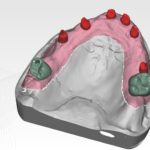

Bridge provisoire transvissé réalisé au laboratoire :

Ce bridge a été réalisé en technique d’impression numérique avec création de la fausse gencive par maquillage de surface